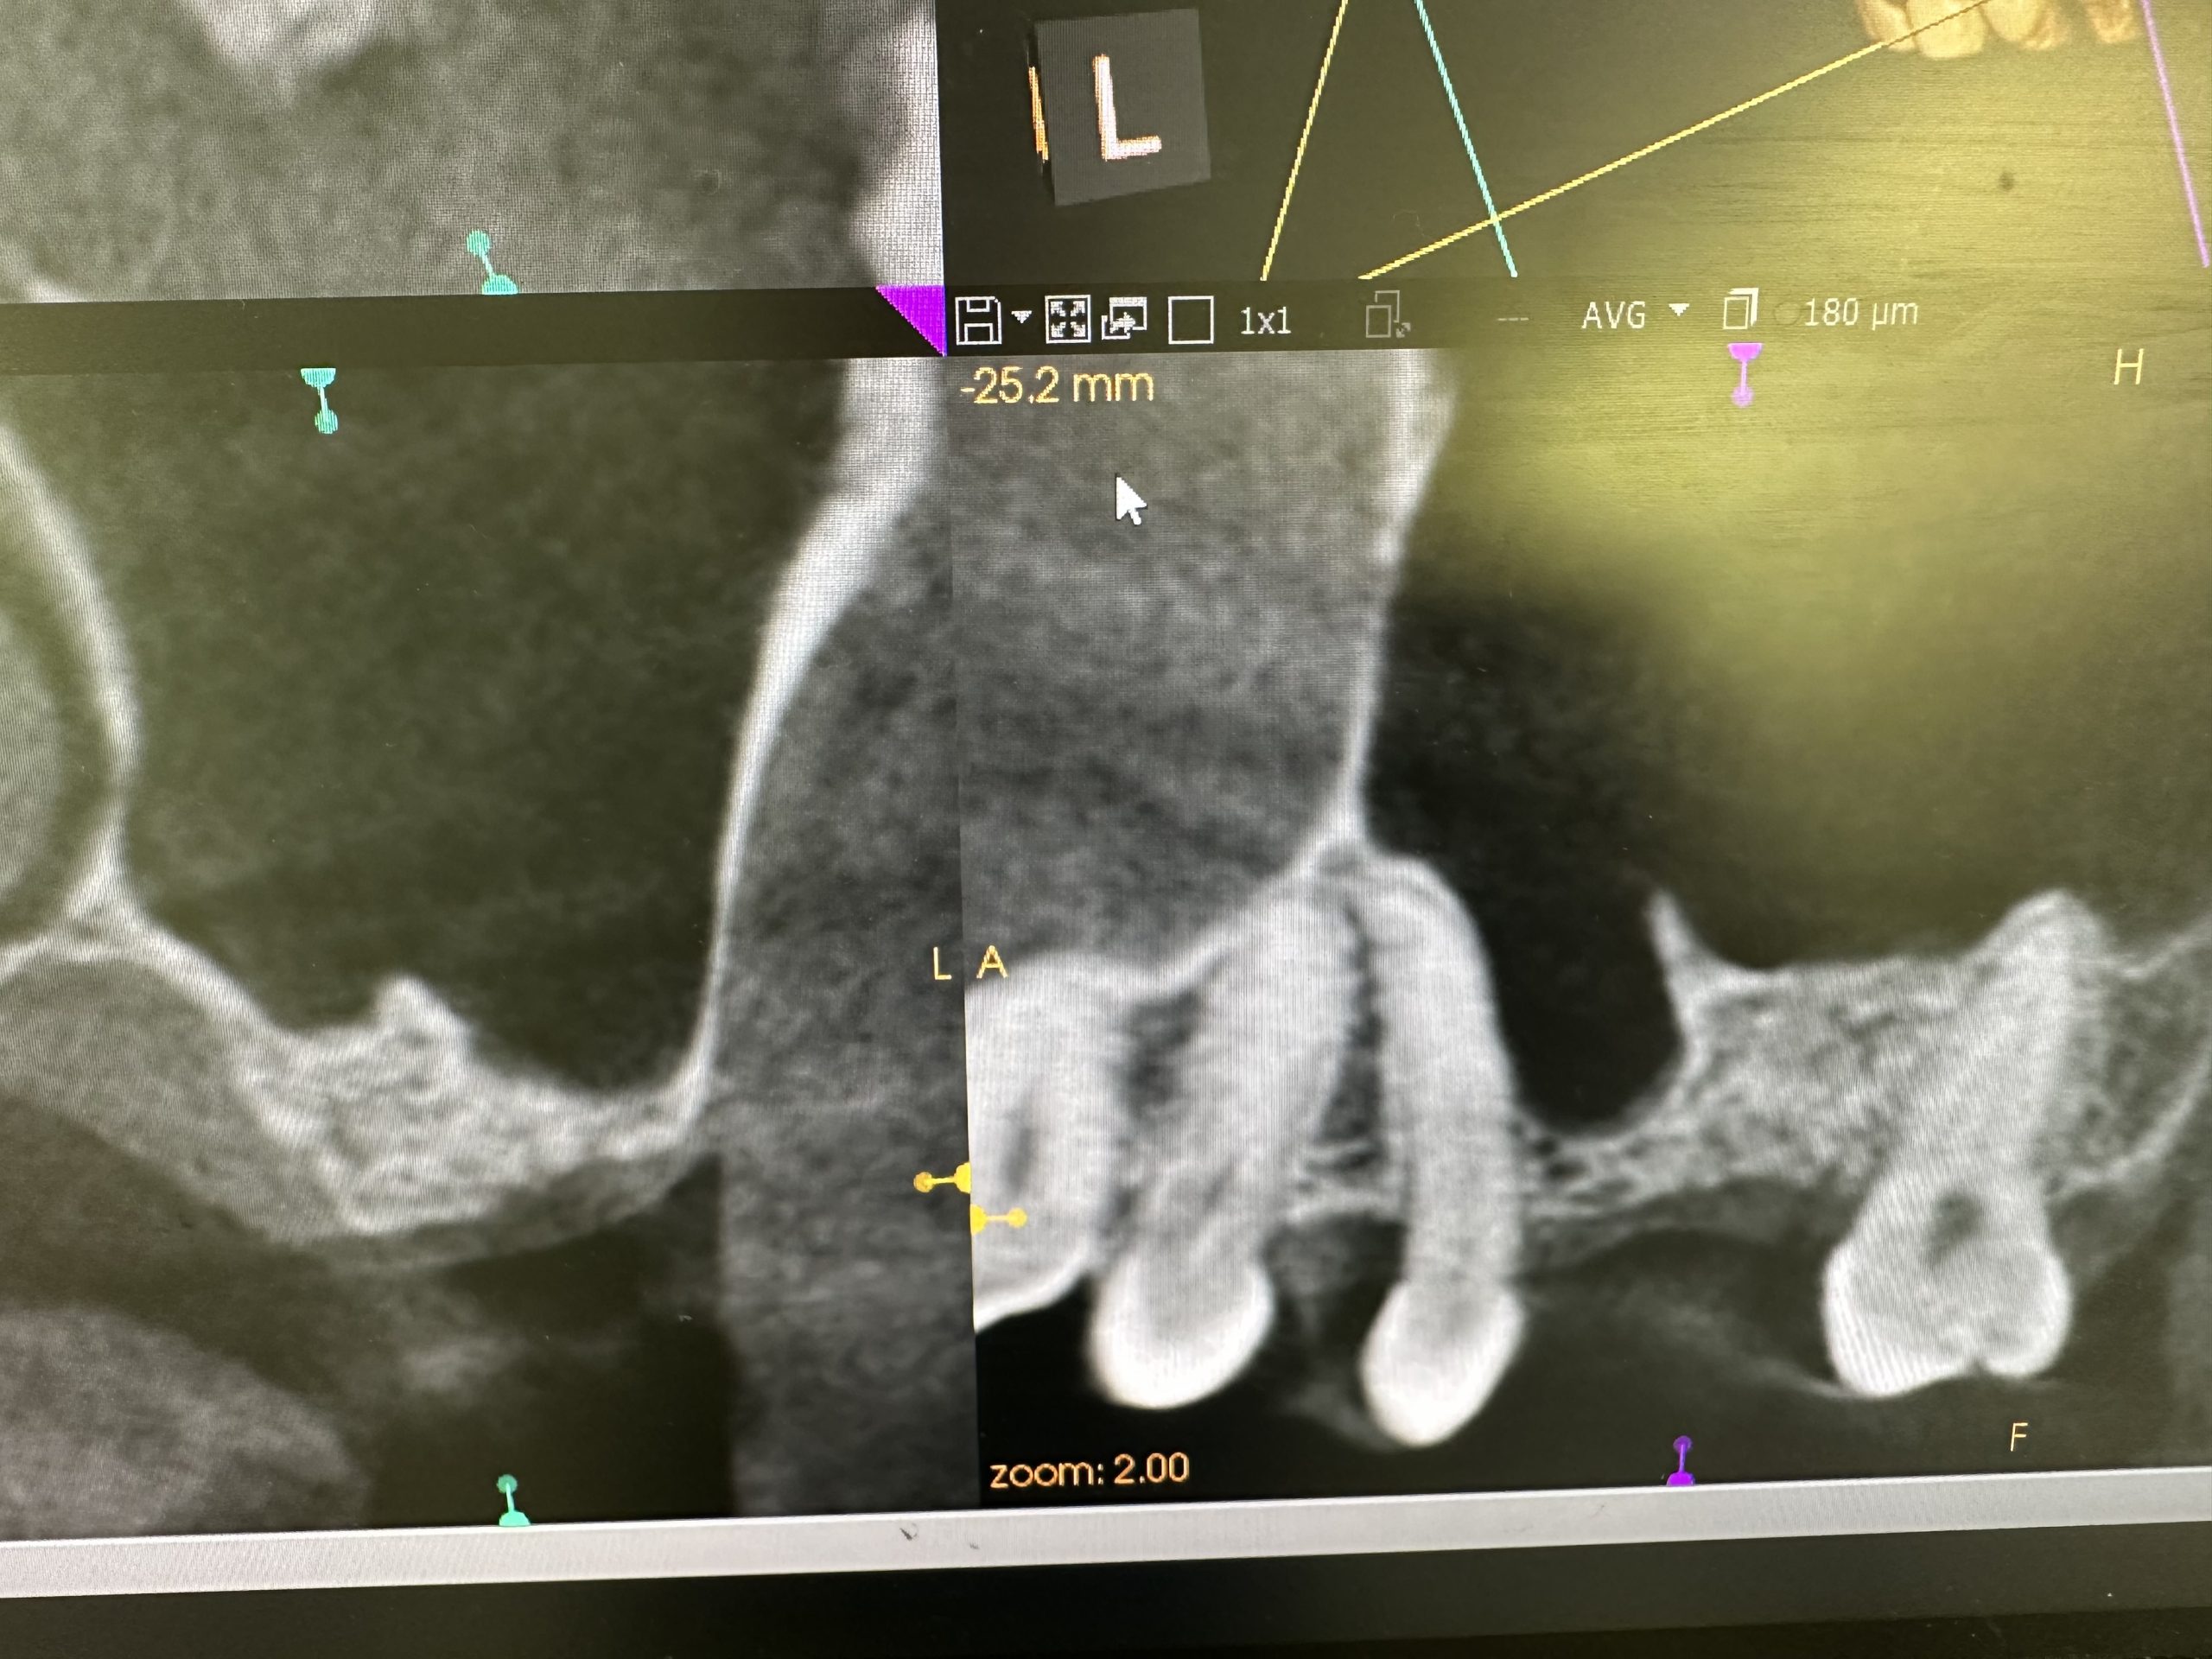

新大久保歯科医院